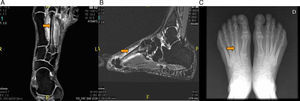

(A) Sagittal magnetic resonance imaging (MRI) in T1-weighted sequence, showing the focal lesion at the level of the talar head with diffuse edema in other bones of right foot. (B) Axial MRI of the foot in T2-weighted sequence, with fat saturation, showing focal lesion at level of the talar head and joint effusion at the level of anterior and posterior tibiotalar joint of right foot.

We present the case of a male HIV-positive patient (diagnosed in 1999), who began antiretroviral therapy with the following regimen. From September 1999 to November of the same year, he took stavudine (d4T) plus didanosine (ddi) and nelfinavir. In November, he changed to zidovudine (AZT) plus lamivudine (3TC) and nevirapine, which he maintains until July 2008, when he began with emtricitabine, plus tenofovir, as well as nevirapine, until the present time. In 2011, he came to the rheumatology clinic with a 2-month history of pain in the dorsum of his right foot, with no previous injury. He underwent bone scintigraphy using Tc-99m, which revealed a severe trauma in the naviculocuneiform region of the right tarsus and a focal lesion of the third metatarsal bone of the right foot, suggestive of a stress fracture (last densitometry, T-score in femur: −2.3 standard deviations [SD]; T-score in spine: −2.4 SD) (Fig. 1A). Magnetic resonance imaging (MRI) showed a clear signal alteration in midfoot, which was manifested as a somewhat lower signal intensity in T1 and an increase in short tau inversion recovery (STIR) sequences, with a discreetly higher signal intensity at the base of the third metatarsal bone. The suggested diagnosis was a stress fracture of right midfoot affecting the naviculocuneiform joint, at the cuboid and third metatarsal bone of the right foot (Fig. 1B). He was treated with nonsteroidal anti-inflammatory drugs (NSAID) and rest. Three months later, the fracture had healed without side effects. In 2012, after an overexertion, the patient presented with mechanical pain in the region of the metatarsus of the left foot. As another stress fracture was suspected, he underwent MRI, which revealed bone edema in the diaphysis of the second metatarsal bone, and in the neighboring soft tissue, consistent with a stress fracture of the second metatarsal bone of the left foot (Fig. 2A and B). He was treated with rest and conservative measures and, the symptoms disappeared in 2 months (plain radiography showed an image of a fracture callus in the diaphysis of the second metatarsal of the left foot (Fig. 2C). On the 30th of January of 2014, the patient returned to the rheumatology clinic, with an increase in the volume of right ankle after another overexertion (a simple walk). Given the possibility of another fracture, he was studied by MRI, which showed a linear image at the level of the talar head, adjacent to the talonavicular joint. He also had a subchondral lesion at the level of the talus (talonavicular joint) with an irregular increase in the talus (Fig. 3A and B).

With a diagnosis that suggested stress fracture of the right talus, the patient was treated with complete rest, the use of 2 crutches, and painkillers. After 3 months, his clinical improvement was complete. The improvement was observed in a new MRI.